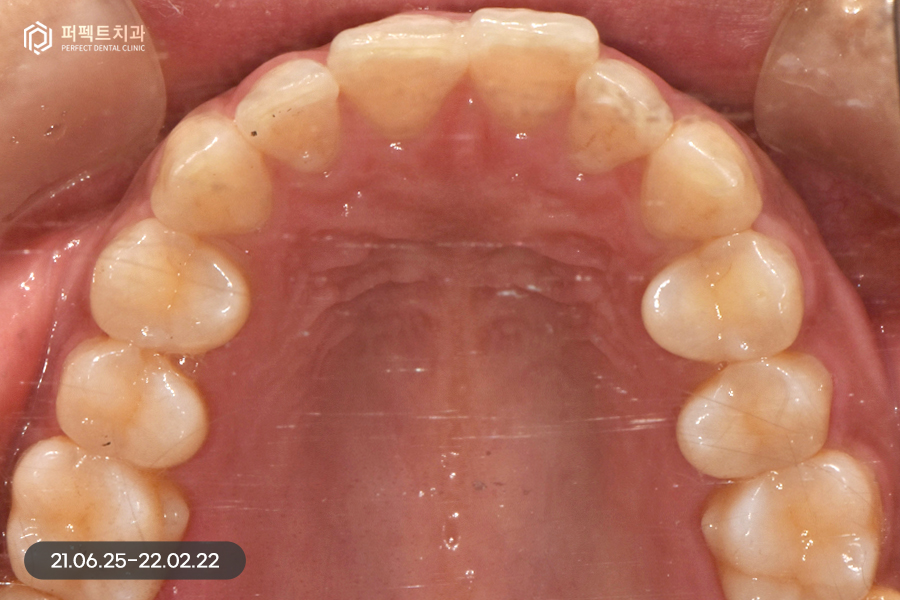

사진으로 보았을 때 큰 문제가 없어보이지만 실제로는 위 아래 치열이 삐뚤빼뚤하고 아래 치아의 경우 위 치아보다 더 틀어짐이 심했는데요. 그렇기 때문에 부분교정을 5개월 정도 진행하였습니다.

교정 후 치아가 가지런하게 펴졌는데, 교정을 하면 항상 생기는 문제점 중 하나가 바로 고르지 못한 치아들이 가지런하게 펴지면서 잇몸 사이 공간인 블랙트라이앵글입니다.

위 환자분도 마찬가지로 블랙트라이앵글이 발생했고, 이 공간을 해결함과 동시에 치아 색상도 하얗게 변화를 주길 원하셨습니다. 그렇기 때문에 위, 아래 6개 치아를 라미네이트 진행하였습니다.